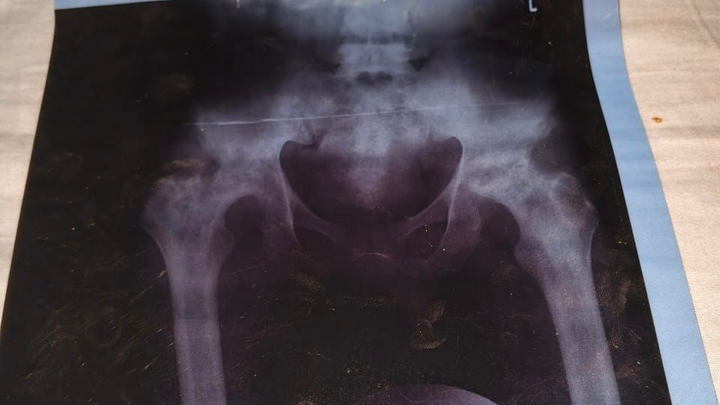

Benjamin Asimeng, a 25 year old determined young man and one of four children raised by a hardworking single mother. For the past two years, Benjamin has been living with persistent and worsening pain in his hips. After finally seeking medical attention, he was diagnosed with avascular necrosis — a serious condition that causes the bone tissue in the hip to die due to lack of blood supply.

Recently, with the help of generous friends, Benjamin was able to visit St. Joseph’s Hospital in Koforidua, a facility well known for its specialized care in bone-related conditions. The news was devastating ,his condition has significantly deteriorated, and he now urgently needs surgery on both hips to prevent further damage and permanent disability.

Each hip surgery costs 72,000 Ghana cedis, bringing the total needed to 144,000 Ghana cedis. This life-changing procedure will relieve his pain, restore his mobility, and give him a chance to rebuild his future.